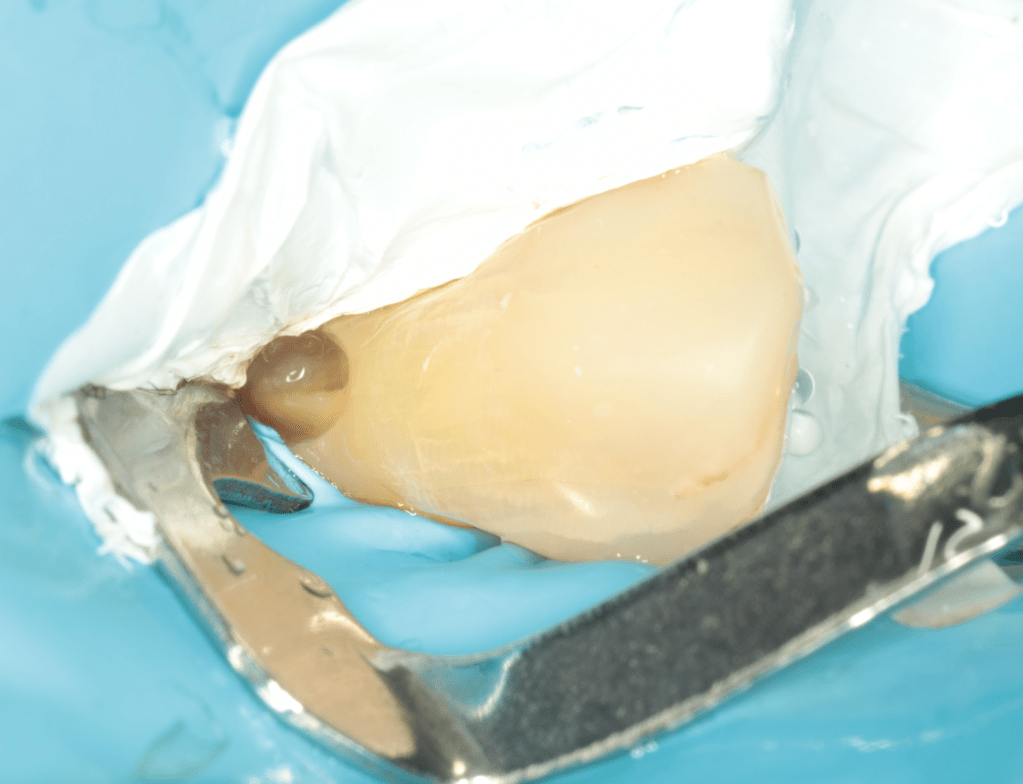

REIMPLANTES

Intencional por dificil acceso coronal y quirúrgico

Reinplante por fracaso de tratamiento

Reimplante, istmo apical, curación cortical palatina 1 año